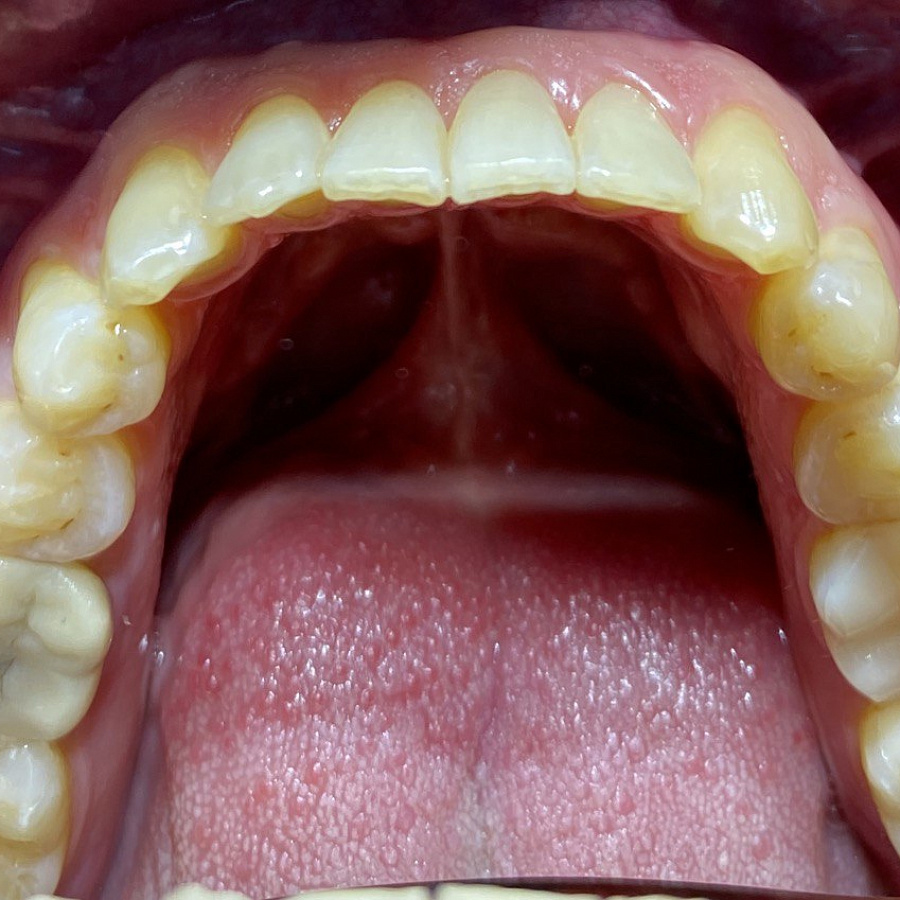

Пациент обратился с жалобами на неровные передние зубы верхней и нижней челюстей.

Диагностика показала:

-

сужение зубных рядов,

обратное перекрытие в области фронтальных зубов слева,

разворот по оси передних зубов верхней и нижней челюстей,

стираемость эмали зубов,

индивидуальную микродентию 12 и 22 зубов.